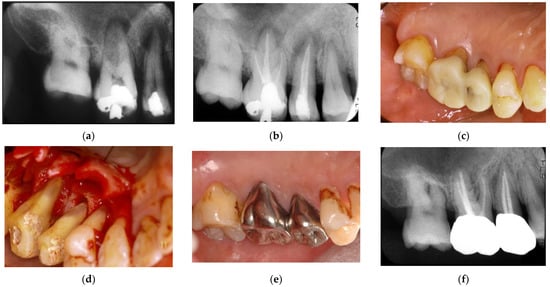

Figure 4. Clinical case 3. Female, age 73 yrs. (a) Intraoral view of the lower right canine at baseline, presenting gingival swelling and pus discharge at the mesial pocket. (b) Preoperative periapical radiograph showing that the “bone” defect was due to advanced periodontitis. (c) Flap retraction and debriding of the defect, presenting the piece of cementum (arrow). Periodontal regenerative treatment with enamel matrix derivative was performed. (d) Fixed prosthesis inserted 5 years later, with healthy gingiva (PD < 2 mm). (e) Follow-up periapical radiograph.